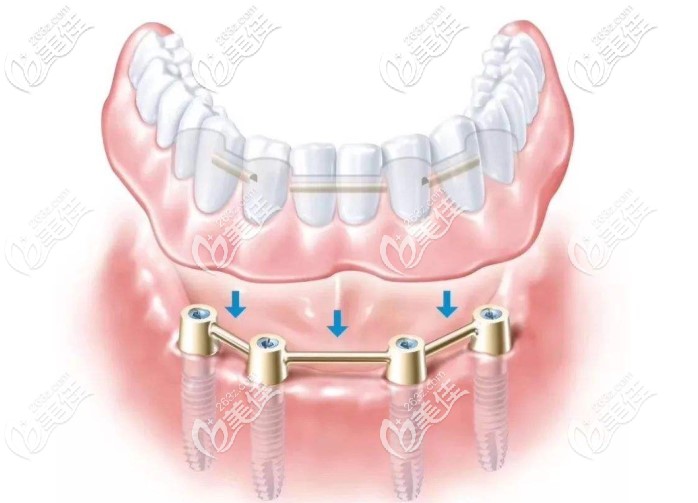

1、A11-on-4種植技術

A11-on-4種植技術就是一次性植入4顆人工牙根固定半口牙橋,恢復半口咀嚼功能,術后就能戴牙,當天回家就能進食。好處是,為顧客降低了種牙風險,節(jié)省了費用,節(jié)省了時間。

allon4種植牙圖片▼